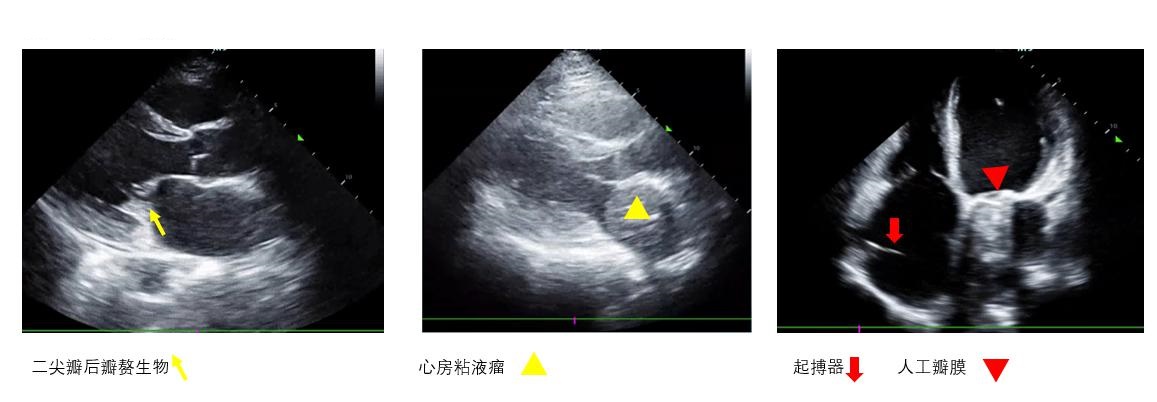

D、瓣膜通过观察瓣膜开合节律和频率评估瓣膜功能及心律失常,二尖瓣开放程度(EPSS)协助评估左心室收缩功能。瓣膜区彩色多普勒超声可评估瓣膜反流、狭窄情况。重度主动脉瓣反流如不能短期内进行外科干预者影响VA-ECMO实施效果(图 6右)。室壁无增厚的右室扩张合并急性三尖瓣、肺动脉瓣反流提示可能存在肺动脉栓塞。呼吸衰竭肺水肿者检查有无二尖瓣脱垂(图 6左)、重度二尖瓣反流。不管是原发还是继发严重瓣膜问题,均可能会在ECMO实施时影响支持效率,因此,建议在ECMO准备阶段筛查瓣膜功能。

F、异物观察心腔内、瓣膜上有无异物(图 7),可协助明确病因并指导进一步治疗。